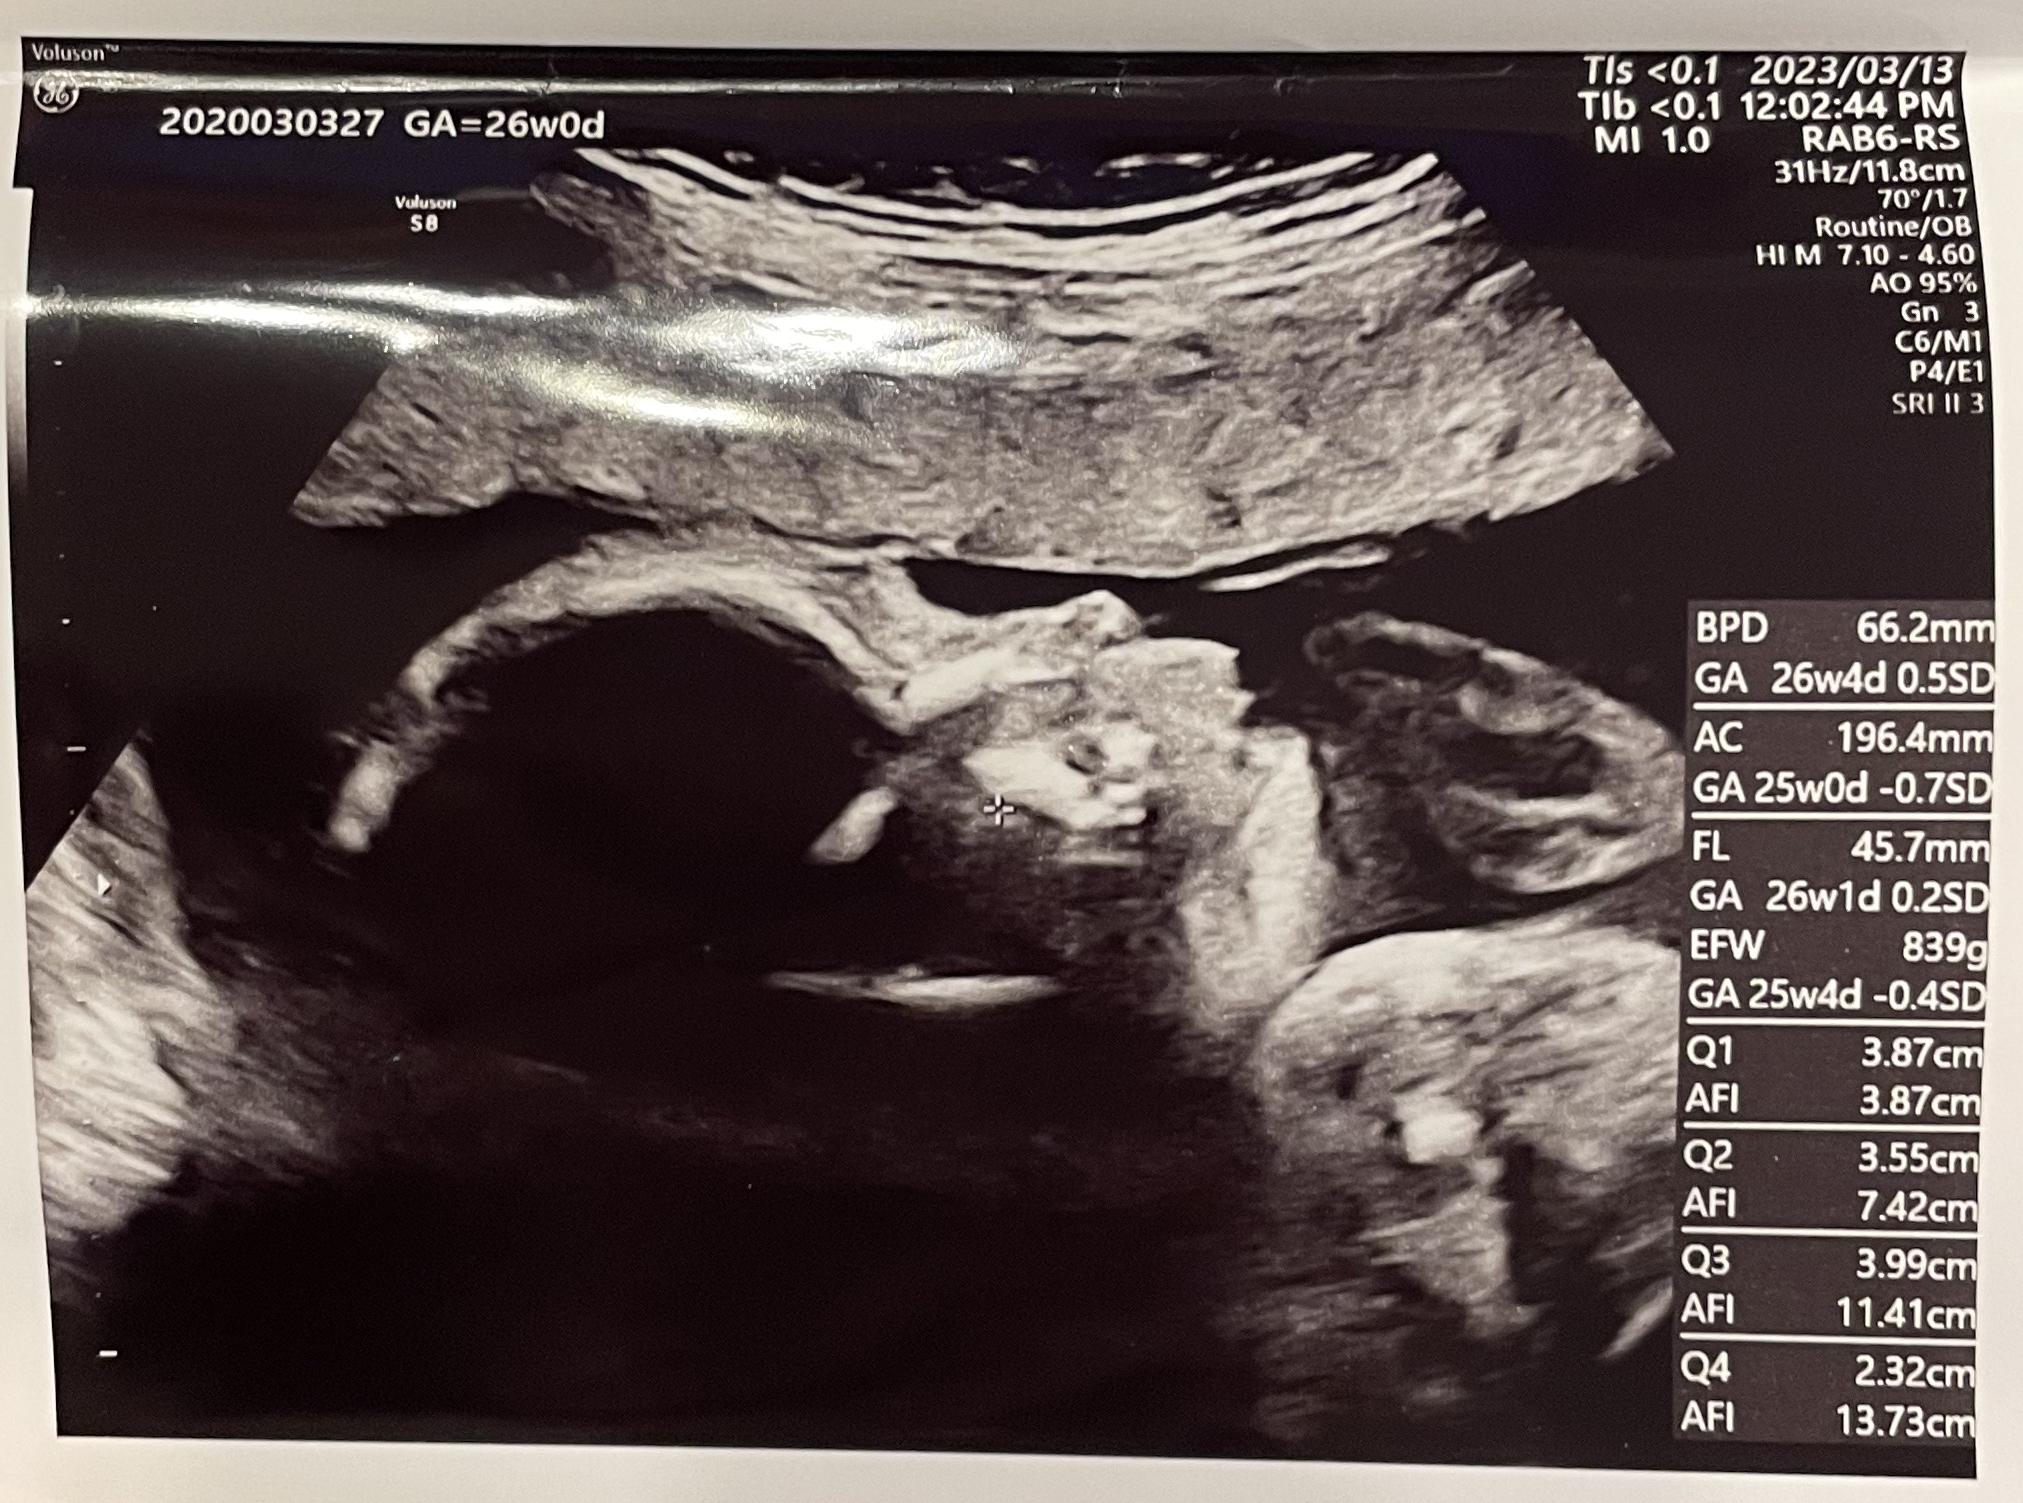

任意の経腹エコー

前回、悩んでいた任意の経腹エコーですが、今回は受けることにしました!

1人目の時に20日間早く生まれてしまったので(ギリギリ早産ではなかった)、今回は赤ちゃんがお腹にいる時間を堪能したいと思ったからです。

生まれてしまえば当然お腹の中に戻ることはできず…(当たり前ですが)、今お腹の中にいる状態の赤ちゃんのお顔が見たいなぁという気持ちで希望しました。

まーるいおでこが可愛くて……!

1人目の時は自分が母親になるということがまだしっくり来ていなくて、半分ふわふわした不思議な気持ちで見ていたエコーでしたが、今回はエコーの写真からして可愛さで胸がギュッとなります。

おててらしきものも見えました。いつも口元に手がある気がします。